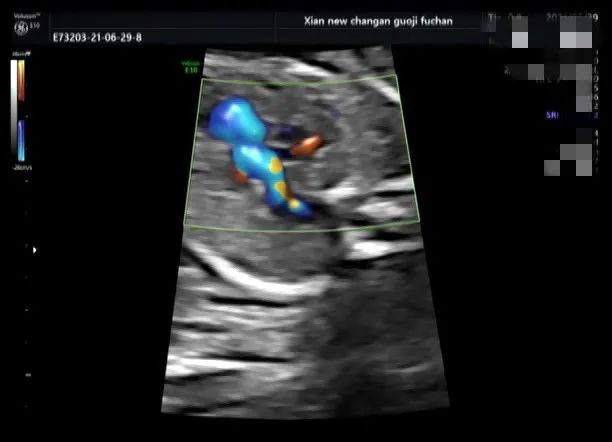

脐带打结是产科胎儿窒息的高危因素之一,利用产前超声检查能够提供准确有价值的诊断依据,我院自 2020 年 10 月至今共产前诊断处 4 例脐带打结。

产科医生向家属告知病情,因 4 例孕妇孕周都在 38W 以上,家属要求行剖宫产手术,娩出婴儿,Apgar 评分:10 分。外观无畸形,脐带中部近胎儿处见真性打结。

脐带真结较为少见,是脐带走形异常或脐带过长在宫内形成环套,胎儿活动穿越环套所致,往往引起不同程度的并发症,易引起胎儿宫内窘迫,严重者可致胎死宫内。

产前超声如怀疑脐带打结,需高度重视,孕期加强监护,注意可疑处脐动脉及脐静脉内径及血流动力学变化,3D 彩色多普勒高分辨仿真血流技术可立体、直观显示脐带形态结构及血流,对脐带打结有一定的诊断价值。